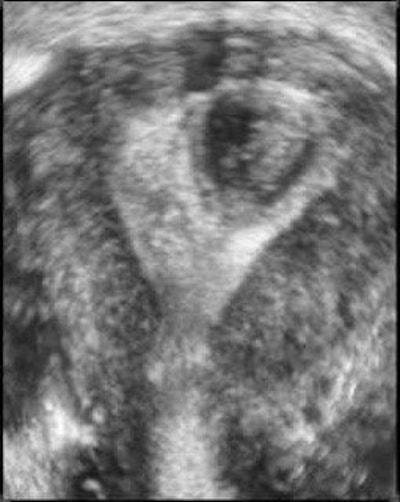

| Three-dimensional ultrasound images showing submucosal fibroids. Images courtesy of Dr. Beryl Benacerraf. |

Other instances in which 3D is helpful include identifying the presence and nature of submucosal fibroids, effectively performing a "virtual hysteroscopy."

In one study of 43 patients with abnormal uterine bleeding, Benacerraf and colleagues found that a 3D coronal view of the uterus was helpful in detecting polyps or fibroids in 35% of cases. The polyps were suggested but ill-defined on 2D ultrasound, she said, and 3D clarified the findings.

The same study also found that turning on the 3D capability wasn't necessary or worthwhile if the 2D scan appeared normal or showed a well-defined finding.